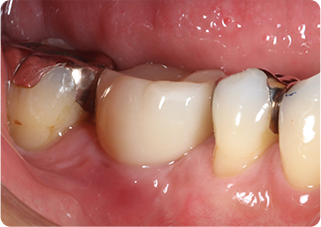

精密根管治療①

術前

術後

| 主訴 | 奥歯で噛むと痛い |

| 治療期間/回数 | 1ヵ月、3回 |

| 価格(税込) | 88,000円(税込) |

| リスク・副作用 | 病変再発、歯根破折の可能性 |

| ポイント | う蝕検知液を用い、むし歯の取り残しが無いようにし、ラバーダム防湿を行い、無菌的に根管治療を行った。根管充填材は、殺菌作用の強い保険適応外のMTAセメントを使用した。 |